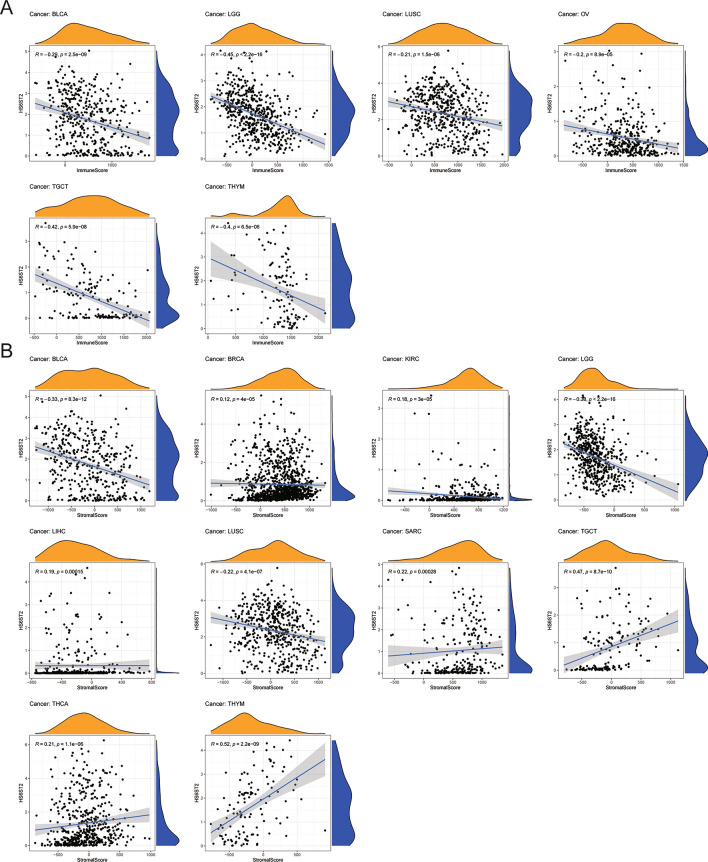

Relationships between HS6ST2 expression and TME factors

Accumulating evidence implies that the TME is necessary for tumor development and incidence33. Our pan-cancer study found a negative correlation between immune and stromal scores and HS6ST2 expression in lung squamous cell carcinoma, bladder urothelial carcinoma, and brain lower grade glioma (Supplementary Table S1). As seen in Fig. 8A,B, HS6ST2 expression was positively correlated with stromal scores in testicular germ cell tumors and thymoma and inversely correlated with immune scores, respectively. Our findings imply that HS6ST2 may affect the immunological tolerance of cancer by altering the TME.